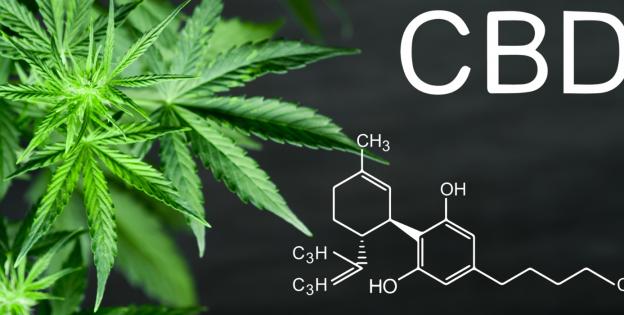

- CBD

El extracto de CBD puede reducir hasta el 50 % las convulsiones en niños con epilepsia